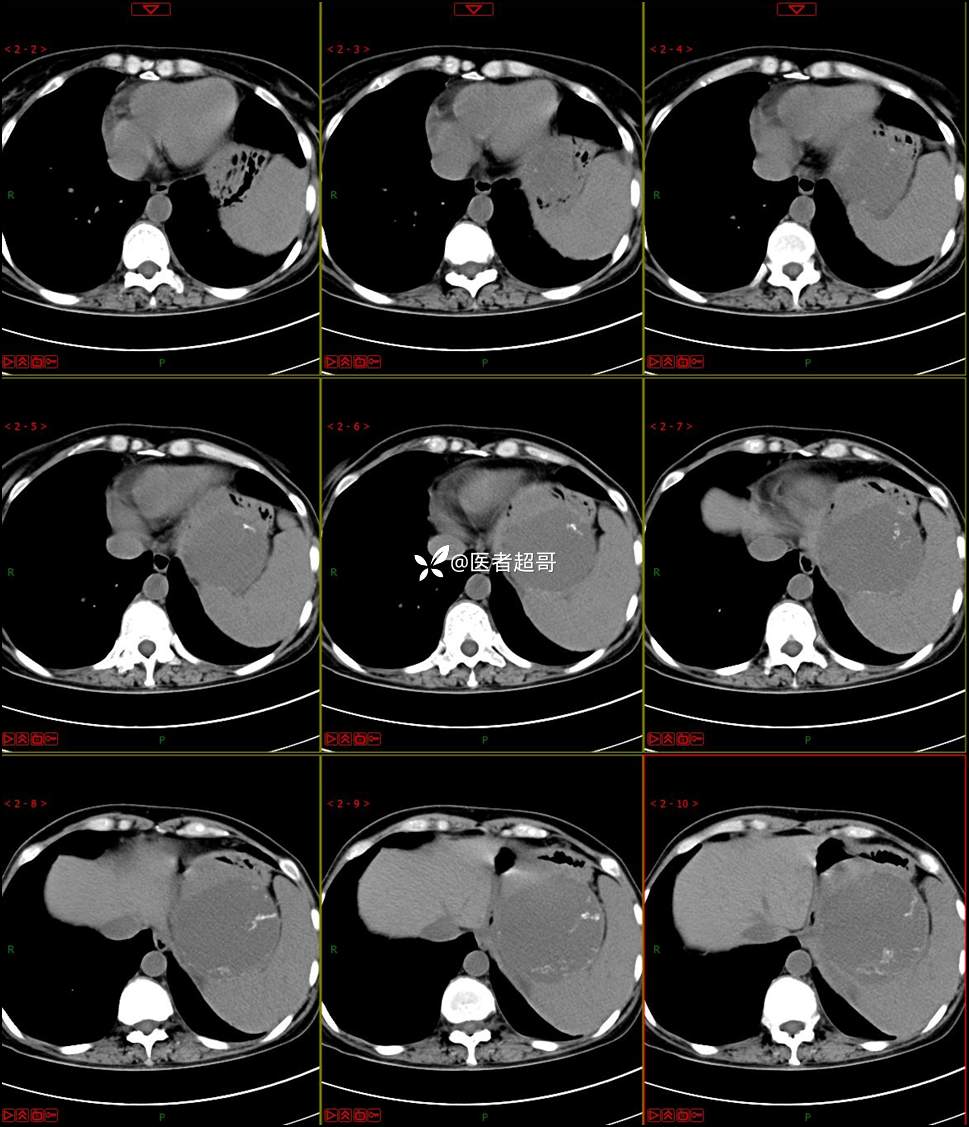

【影诊笔记768】肾脏肿瘤?肾上腺肿瘤?请诊断分析!

女 57岁 0200908 01

主 诉:发现左肾肿物7月余

现病史:患者7月前因左侧腹部疼痛不适,就诊市人民医院,行CT平扫:左侧肾上腺区混杂密度肿块,考虑肿瘤合并出血,行保守治疗后症状缓解出院,左侧下腹部及左侧髋部疼痛不适,无尿频、尿急、尿痛,无肉眼血尿,无寒战、发热,今患者为求进一步诊治,就诊我院,门诊以“左肾肿物”为诊断收入院,患者自发病以来,神志清,精神可,饮食睡眠可,小便如上述,大便正常,体重未见明显改变。